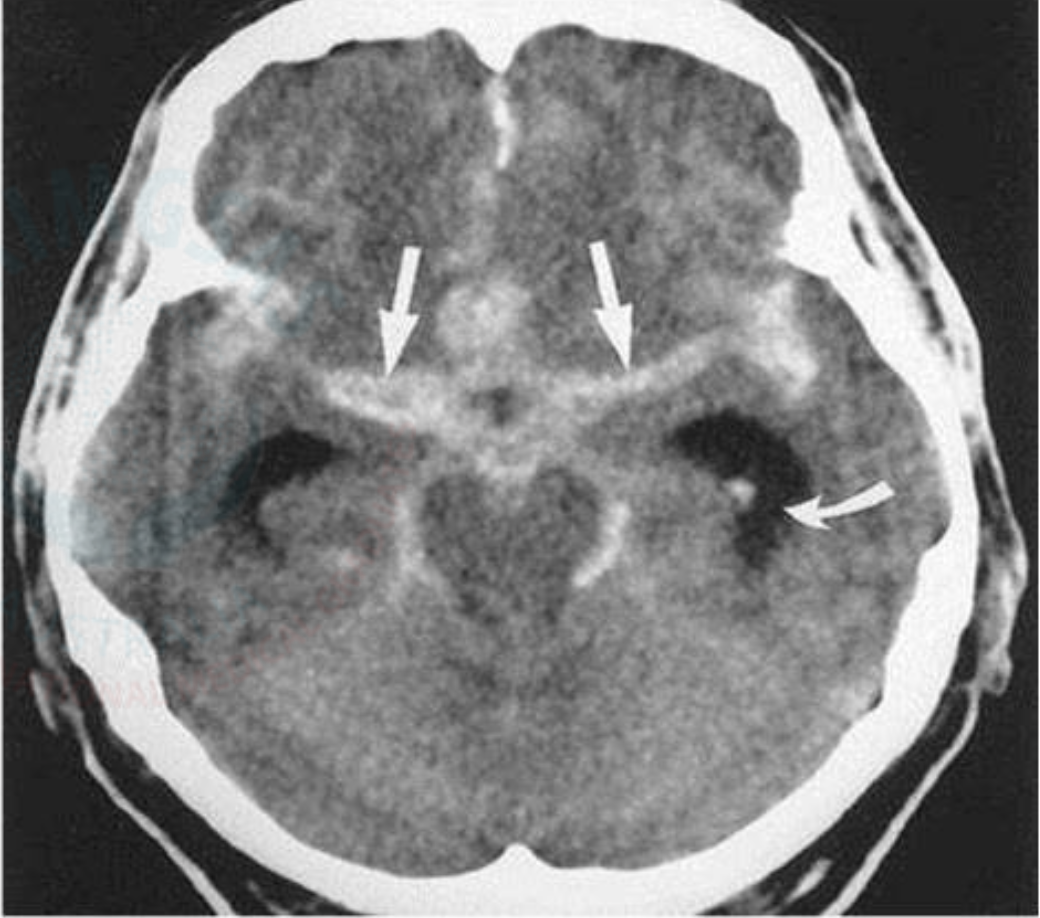

Headache: Subarachnoid Hemorrhage CT Imagen

Areas of hyper density within the cisterns and sulci

Headache: Subarachnoid Hemorrhage INVESTIGATIONS

Dx: 1) CT Head – investigation of

choice

2) Lumbar puncture is used if CT scan is

negative – Homogenous blood staining of CSF

and Xanthochromia are diagnostic of SAH